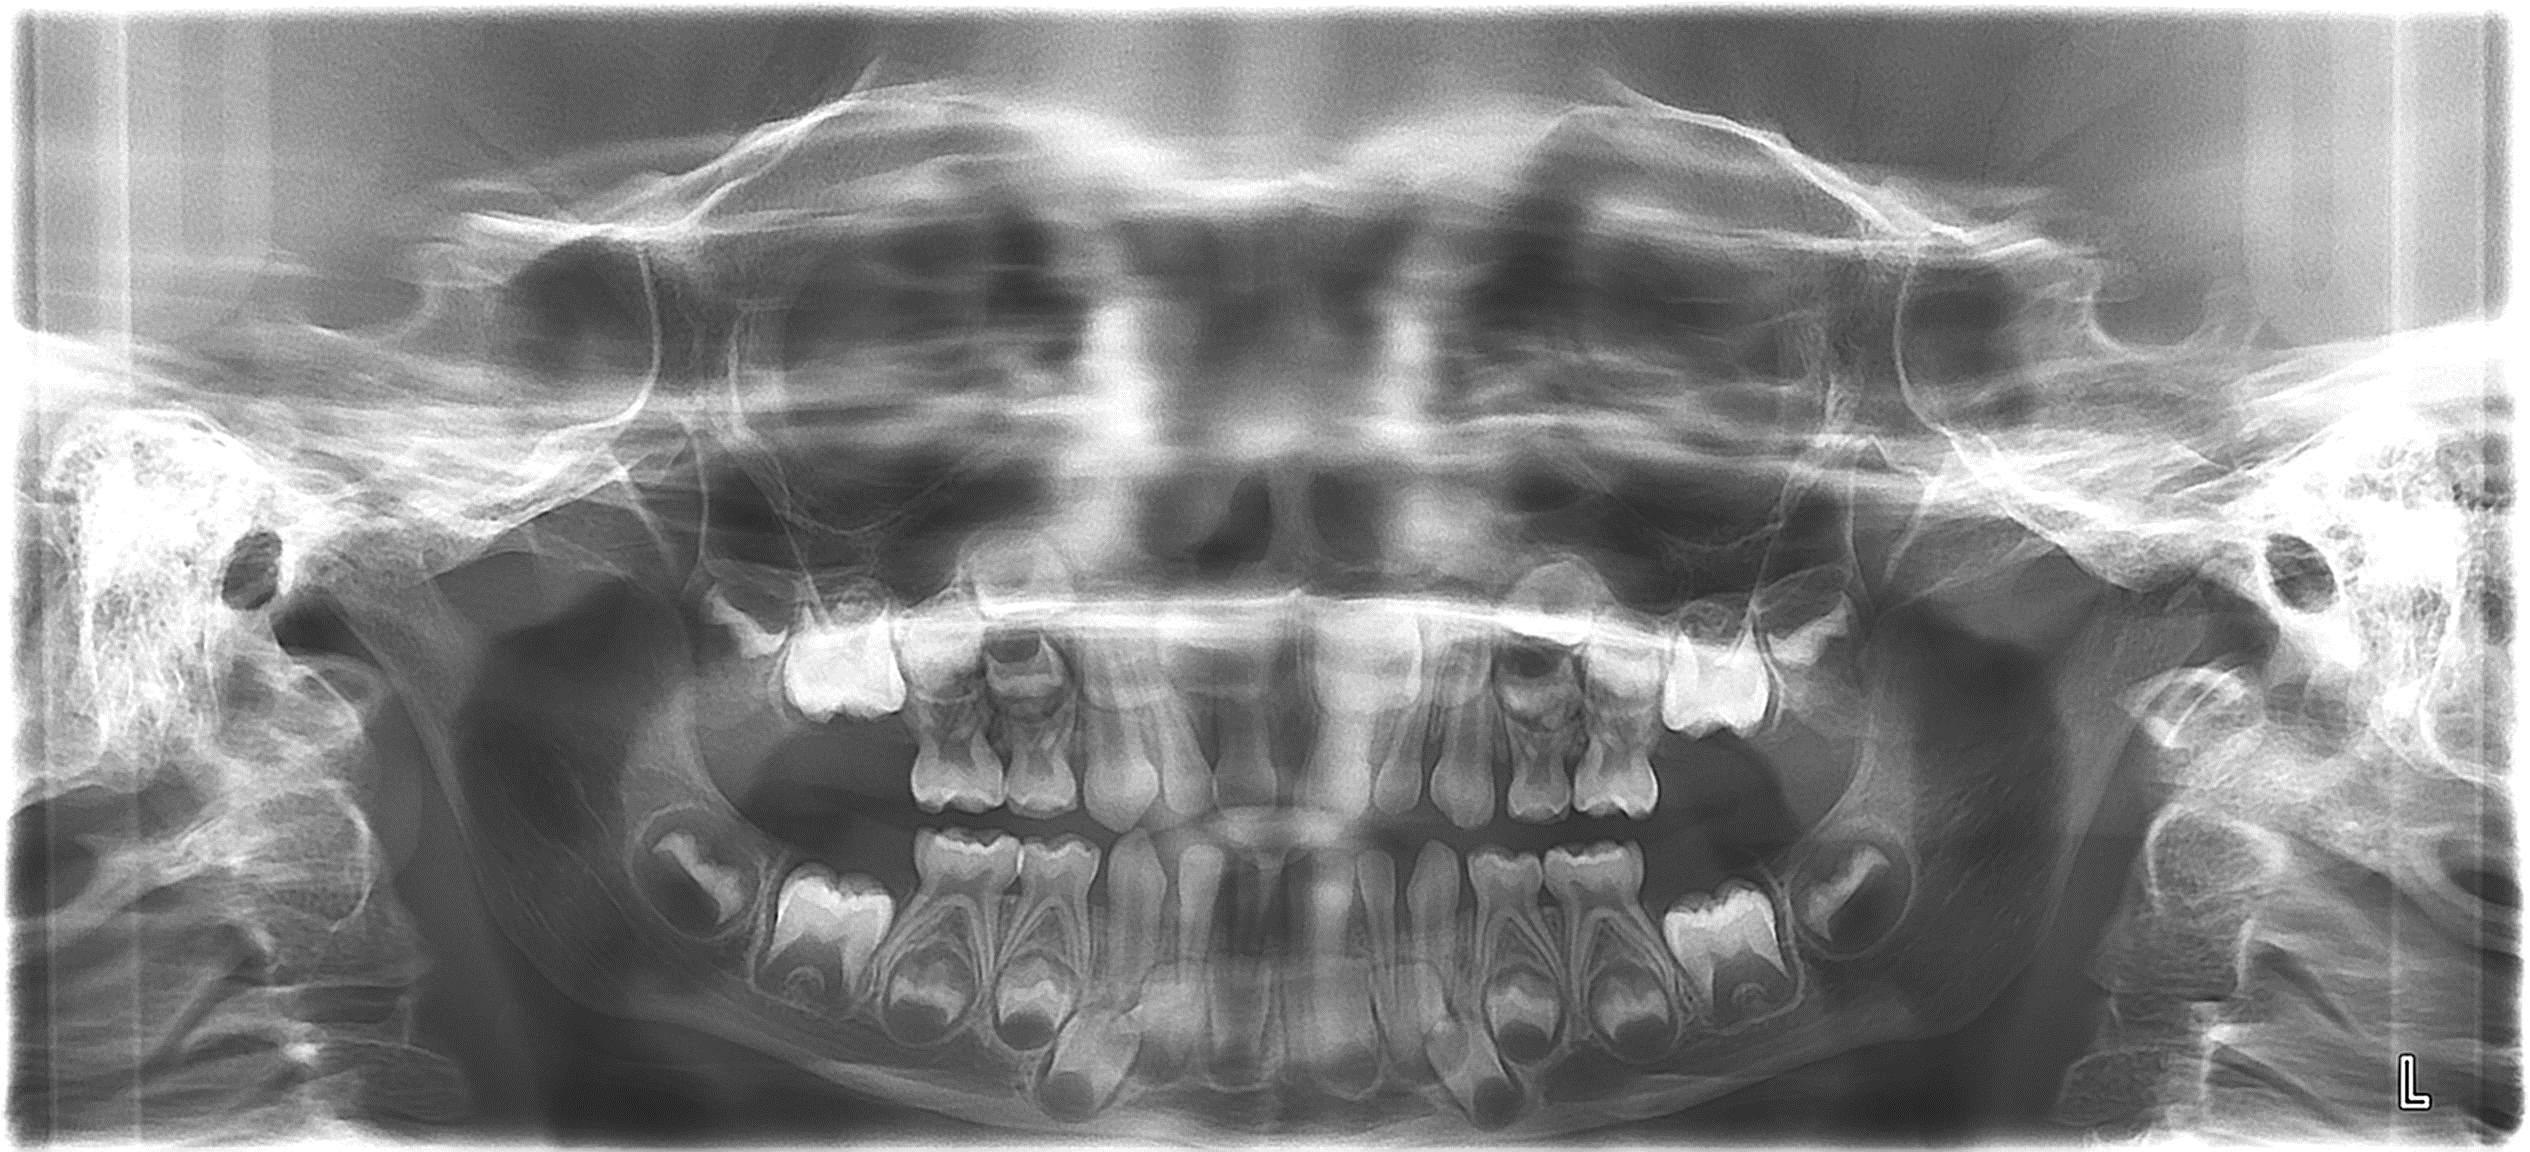

bilan des radiographies début et en cours de traitement

bilan de début et en cours de traitement